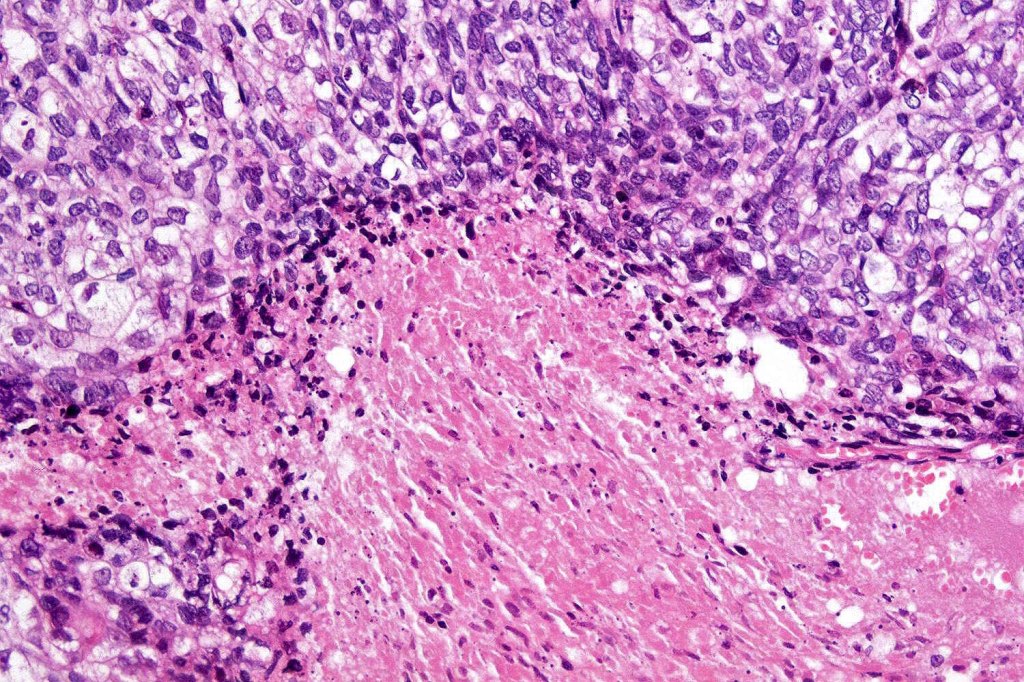

•Comedo type necrosis commonly present

•Well differentiated examples can be deceptive unless one looks carefully for pleomorphism, necrosis, excessive mitotic activity and abnormal mitoses. Be careful diagnosing sebaceous adenoma, particularly large examples arising in the elderly

•Tumors are composed of an admixture of darkly staining basaloid cells with hyperchromatic or vesicular nuclei and more obvious sebaceous cells with eosinophilic, bubbly, multivacuolated cytoplasm frequently indenting the nucleus (scalloped)

•Often mitoses are numerous and abnormal forms evident

•Variable Lymphovascular invasion & perineural infiltration